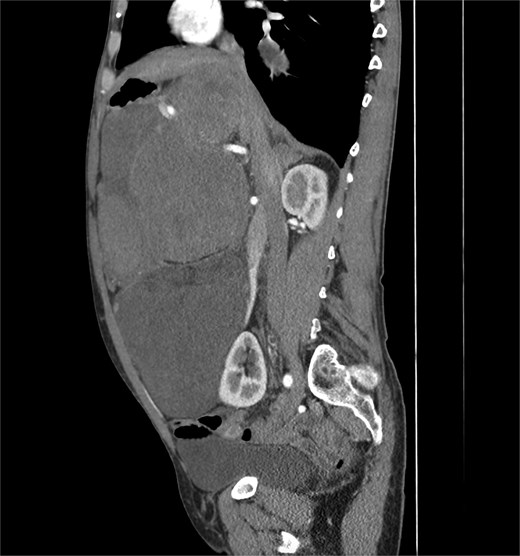

A 53-year-old man, ex-smoker and occasional alcohol consumer, reported several months of postprandial dyspepsia and increased bowel movements (3–4 per day), without weight loss or systemic symptoms. Physical examination revealed a distended, somewhat tense abdomen without focal tenderness. Laboratory tests, including complete blood count, biochemistry, and inflammatory markers, were within normal limits. Cross-sectional imaging demonstrated a multilobulated, predominantly solid retroperitoneal mass measuring 35 × 32 × 18 cm. Contrast-enhanced computed tomography (CT) and magnetic resonance imaging (MRI) showed displacement—but no frank invasion—of the inferior vena cava and aorta, encasement of mesenteric vessels, and compression of bowel loops. A notable anatomic variant was an ectopic left kidney located in the right paramedian pelvis. No distant lesions were identified (Figs 1 and 2). Three-dimensional CT angiography delineated the relationship with major vessels and aided operative planning (Fig. 3). After multidisciplinary discussion, primary surgical resection was favored given the well-circumscribed nature of the mass, the absence of metastatic disease, and the patient’s symptoms. Through a midline xipho-pubic laparotomy, a well-encapsulated, firm, tan-white mass occupying most of the retroperitoneal cavity was exposed. Sharp and blunt dissection allowed complete en bloc excision without capsular violation. Estimated blood loss was modest and no vascular reconstruction was required. Grossly, the specimen weighed approximately 12 kg and showed multinodular architecture with focal myxoid areas.